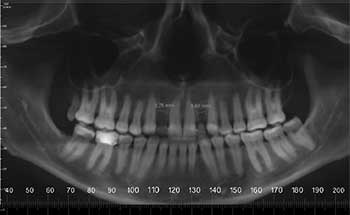

Fig. 7: 18 months progress; UR1 needs mesial root tip.

Fig. 8

Fig. 9